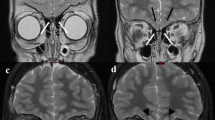

Another paper reported on intracranial ACs that showed an X-linked dominant inheritance pattern [24]. There were four family members who all presented with large, bilateral, symmetric middle fossa ACs [24]. They were all found to have a maternally inherited 720-kb duplication of the Xp22.2 chromosome that was not present in any of the unaffected family members [24]. This chromosome region includes the genes listed in Table 6.

Loss of function of MID1 and ARHGAP6 were found due to breakpoints in the duplication [24]. Here, it seems that genes needed for appropriate disposal (or recycling) of proteins were important in the formation of ACs. The other two genes in the region may not be related to the formation of ACs.